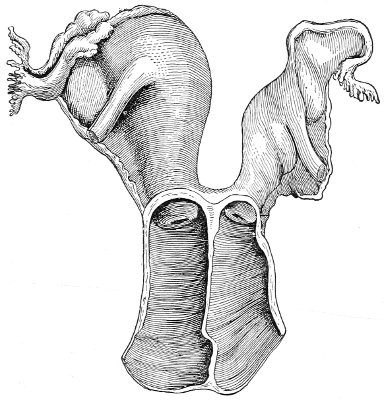

An accurate knowledge of the anatomy and mechanism of the female perineum is essential to an understanding of the nature and treatment of injuries to this structure. The anatomical structures lying between the anus behind and the symphysis pubis in front are those that most directly interest the gynecologist. Proceeding from 57 below upward, we find the following structures lying in superimposed planes: the skin, the superficial fascia, the deep layer of the superficial fascia, the transversus perinæi and the sphincter vaginæ muscles, the anterior layer of the triangular ligament, the posterior layer of the triangular ligament, the levator ani muscle (Fig. 19).

The vagina passes through these structures. They surround and support the ostium vaginæ as the fascia and muscles surround and support the opening of the rectum or the anus. The muscles and fasciæ are attached in the median line between the anus and the vagina, and therefore this part of the body, which is called the perineum, is supported or maintained in its 58 proper position by these various structures. The transversus perinæi arises from the ramus of the ischium and is inserted in the perineum. The bulbo-cavernosus, or sphincter vaginæ, arises in the perineum and is inserted in and about the clitoris. The inner fibers of the levator ani arise from the symphysis pubis and are inserted in the perineum and the lower part of the vagina (Fig. 20). When these muscles contract, their action, therefore, is to draw the perineum upward and forward. At the same time the anus is drawn upward and forward, and so also is the posterior margin of the ostium vaginæ and the lower portion of the posterior vaginal wall.

The vagina has no circular sphincter like the anus, but 59 the vaginal month is kept closed by the action of the transversus perinæi, sphincter vaginæ, and levator ani muscles, which draw the perineum forward, and thus keep the posterior vaginal wall in apposition with the anterior wall.

Fig. 21.—Muscular floor of the pelvis seen from above.

This sling of muscles and fascia, which surrounds and supports the opening of the vagina, may readily be felt in the nulliparous woman by introducing the finger in the vagina and pressing backward and outward toward the ischio-rectal fossa. We then feel plainly, immediately within the ostium vaginæ, a firm resisting band of tissue, apparently about half an inch broad, embracing the posterior portion of the lower vagina. This band is formed by the inner edges of the various muscles and planes of fascia that have been described.

Fig. 22.—Sagittal section showing relations of the several layers of fascia within the pelvic floor (Dickinson).

The vagina extends, as a transverse slit in the pelvic floor, upward and backward, approximately in the direction 60 of a line drawn from the ostium vaginæ to the fifth sacral vertebra. It is approximately parallel with the conjugate of the brim, so that when the woman is erect the long axis of the vagina is inclined at an angle of 60° to the horizon. The vagina is not a vertical open tube: it is a slit in the pelvic floor, in health always closed by the accurate apposition of the anterior and posterior walls (Fig. 21). The anterior vaginal wall is about 2½ inches long in a vertical mesial line. The posterior vaginal wall is about 3½ inches long. The vaginal walls are triangular in shape, being broader above than below. The shape of the normal vagina at the pelvic outlet is shown by Fig. 23. The section here shows the vaginal 61 slit of the shape of the letter H. The portions of the slit extending backward and somewhat outward are called the vaginal sulci or furrows. They are directions of diminished resistance in which tears are liable to occur.